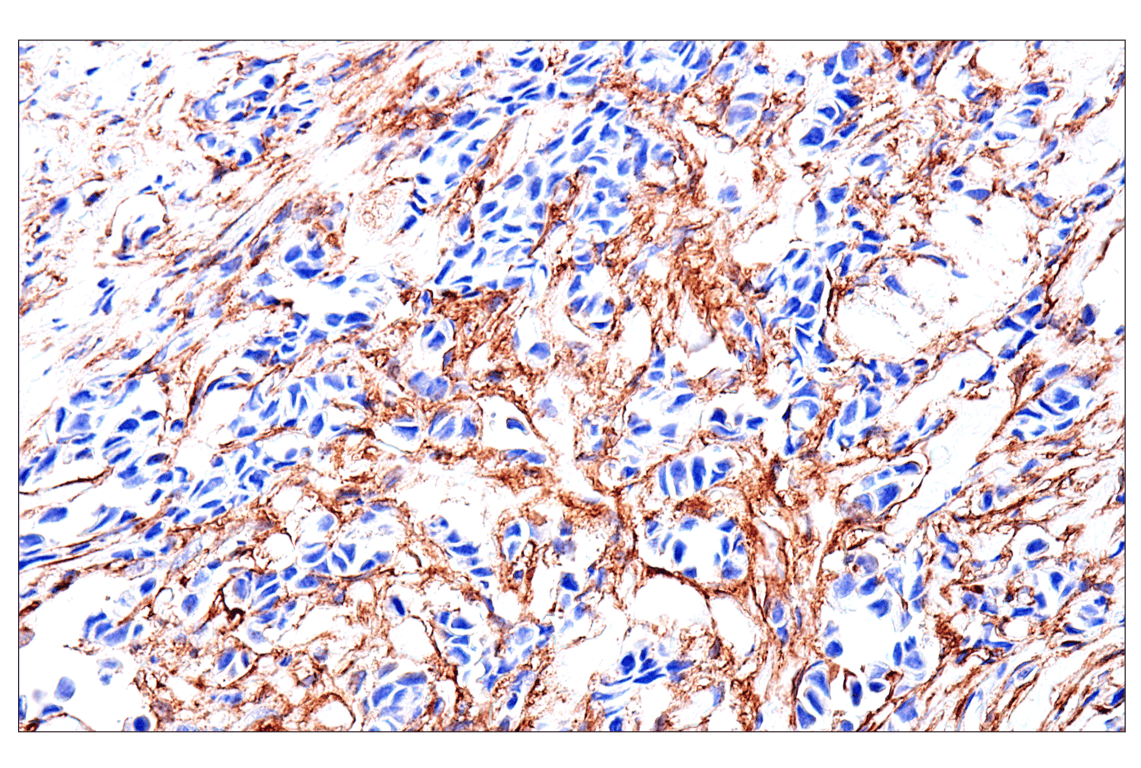

Immunohistochemical analysis of paraffin-embedded human pulmonary sarcoma using FAP (F1A4G) Rabbit mAb. Data were generated using the standard formulation of this product.

Immunohistochemistry Image 4: FAP (F1A4G) Rabbit Monoclonal Antibody (BSA and Azide Free)